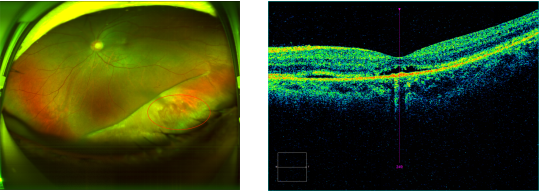

△术前(第一、二幅图)、术后七天(第三、四幅图)的左眼欧堡眼底和黄斑OCT对比图